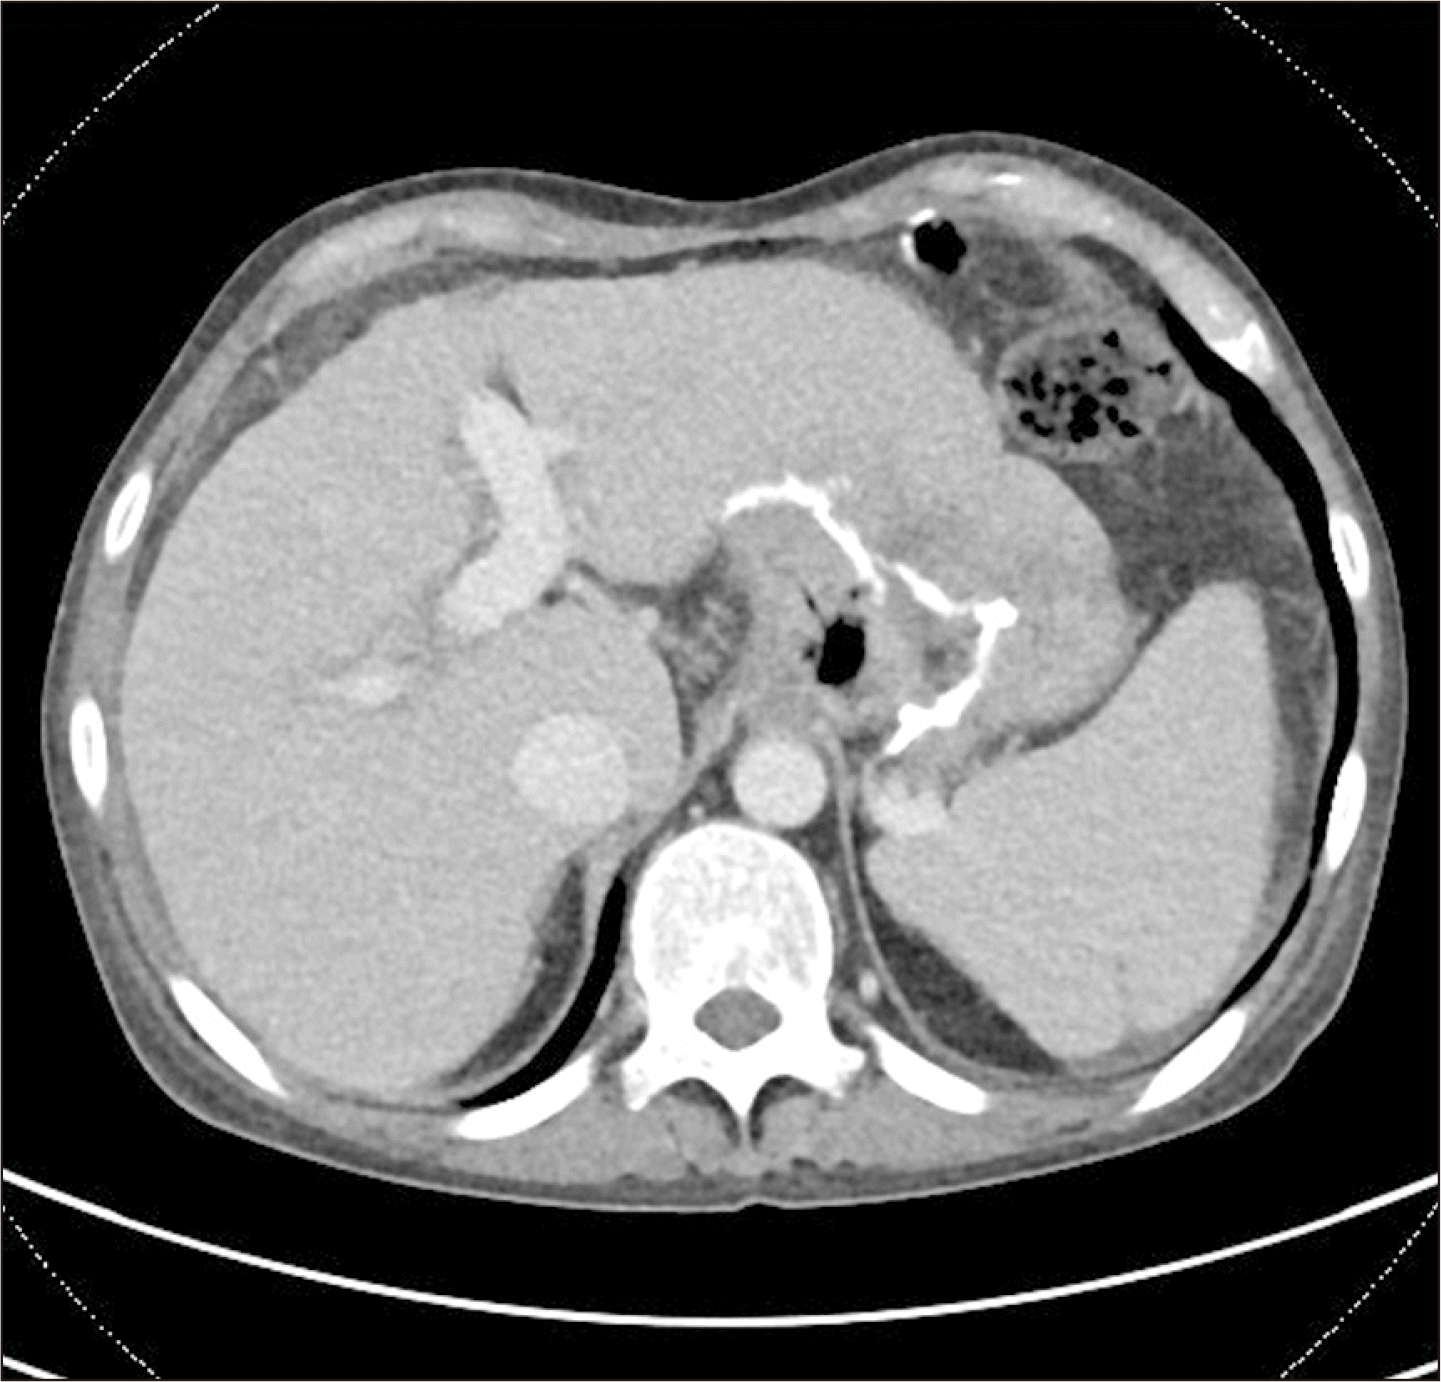

A 43-year-old female patient was diagnosed with acute on chronic liver failure associated with alcoholic liver cirrhosis (Fig. 1) with hyponatremia, and hepatic encephalopathy Grade 3 (Glasgow Coma Scale, GCS 10). Her medical history included partial gastrectomy for obesity in 2002. The patient underwent LDLT. Before transplantation, Rituximab infusion and one session of plasmapheresis were performed due to high titer of cytotoxic antibody. Sodium level was 125 mmol/L, and ammonia level was 231 mmol/L at the time of admission. GCS was 10. Sodium benzoate 4 g/20 mL and lactulose were initiated to decrease ammonia levels in the blood and improve mental status. Ammonia levels started decreasing after sodium benzoate and lactulose treatment, accompanied by slight improvement in mental status. One day before surgery, ammonia levels decreased from 231 mmol/L to 110 mmol/L (Fig. 2), while sodium levels increased from 125 mmol/L to 158 mmol/L. During surgery, a significant blood transfusion was performed, consisting of 8 L blood components - 12 units of red blood cell and 7 units of fresh frozen plasma. Sodium levels during surgery ranged from 150–153. Reperfusion caused severe bradycardia (heart rate 20), corrected by epinephrine 100 mcg IV. Post-LT, the patient was transferred to the intensive care unit. In postoperative period, liver doppler and liver function tests were normal, and postoperative liver computed tomography (CT) scan at postoperative 5th day showed normal findings (Fig. 3). Despite this, the patient remained unresponsive to commands and exhibited a tendency to sleep. Post-surgery ammonia levels decreased to 110 with a declining trend and normalized on post-operative day (POD)#2–3 (Fig. 2). However, the patient’s mental status deteriorated, with GCS score decreasing from 10 to 6. Sodium levels initially increased to 160 but normalized after POD#5. Electroencephalogram showed delta slowing, and Brain CT scan revealed no significant abnormalities. Magnetic resonance imaging (MRI)+diffusion-weighted imaging revealed CPM (Fig. 4). Conservative treatment was initiated, maintaining tacrolimus levels below 5 to prevent CPM progression, and vitamin B (thiamine) supplementation was provided. Levodopa was administered, resulting in improvement in mental status and GCS from 6 to 12 after POD#19.

Figure 1

Pre-operative computed tomography shows acute liver damage and stapling line related with the previous partial gastrectomy for obesity.